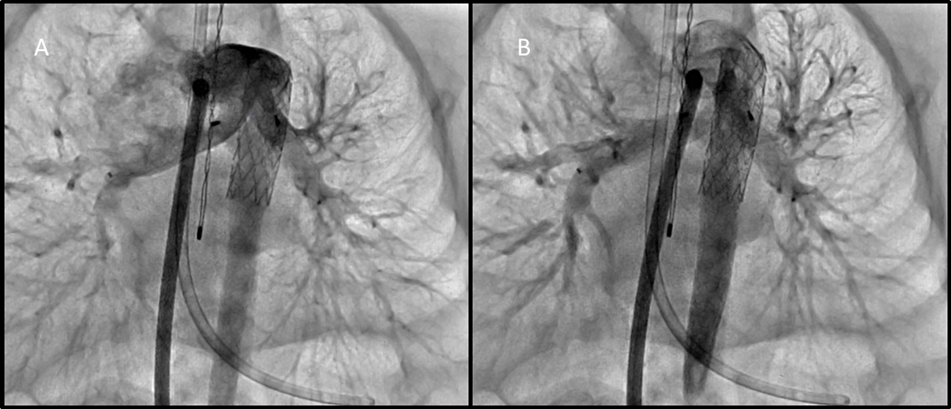

Figure 3

Figure 3. A. Angiographic evaluation of PFRs through a long sheath in the MPA. This first image better demonstrates jailing of the left upper pulmonary artery, with continued flow of contrast into this branch. B. This image demonstrates jailing of the right upper pulmonary artery. There is still flow seen entering this branch.